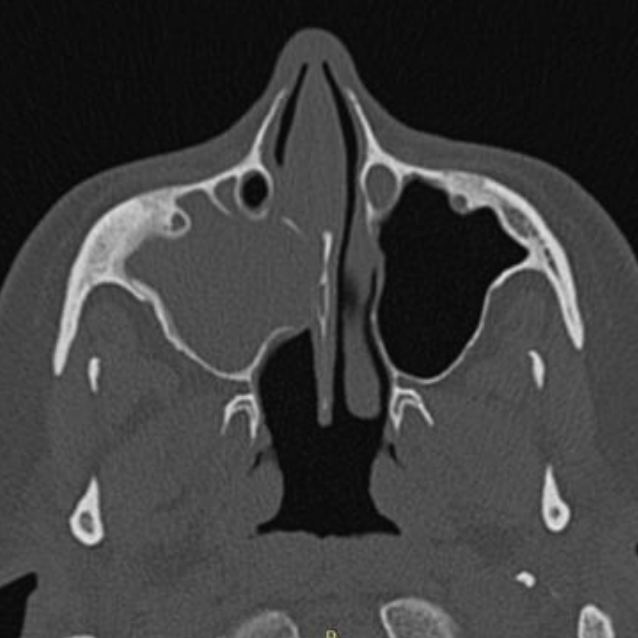

Imagem de tomografia computadorizada em janelamento ósseo, no plano axial, demonstrando obliteração total do seio maxilar direito, associado a erosões ósseas da face nasal do mesmo. Seio maxilar esquerdo sem particularidades.